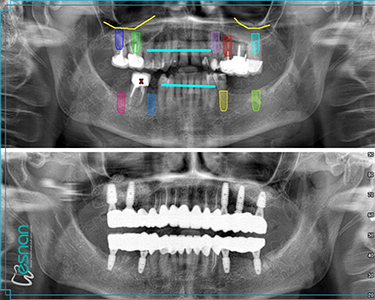

Oral, dental, and maxillofacial radiology is a crucial element in comprehensive dental care. It utilizes various imaging techniques, such as periapical radiographs, panoramic radiographs, cone beam computed tomography (CBCT), and occlusal radiographs. These tools provide valuable insights into the underlying structures of the mouth, teeth, and jaws, allowing dentists to diagnose and treat a wide range of conditions, including dental caries, periodontal disease, infections, tumors, and developmental abnormalities. Early detection and accurate diagnosis through oral, dental, and maxillofacial radiology can significantly impact treatment outcomes and improve overall oral health.

• Planning for dental implants

Oral, dental, and maxillofacial radiology is an indispensable tool in diagnosing and treating various conditions that affect the mouth, teeth, and jaws. Through radiographs and other imaging modalities, dental professionals can visualize structures not readily visible during a clinical examination. This allows for early detection of dental caries, periodontal disease, infections, tumors, cysts, and developmental anomalies, among others. Early diagnosis and accurate assessment through radiographic imaging are crucial for determining the most appropriate treatment course, leading to improved patient outcomes and overall oral health.

Each examination listed above serves a specific purpose in dental diagnostics. Panoramic X-rays provide a broad view of your teeth, jaws, and surrounding structures, while intraoral radiography offers detailed images of individual teeth. Cephalometric X-rays assess facial growth and development, and CBCT scans provide detailed 3D images for complex cases like implant planning and oral surgery. Our experienced team is dedicated to utilizing these technologies to deliver precise and personalized care for every patient.

• Dental Cone Beam Computed Tomography (CBCT)